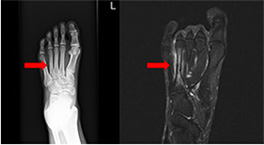

Ⅹ線では診断が難しい早期の疲労骨折もMRIであれば診断できます。